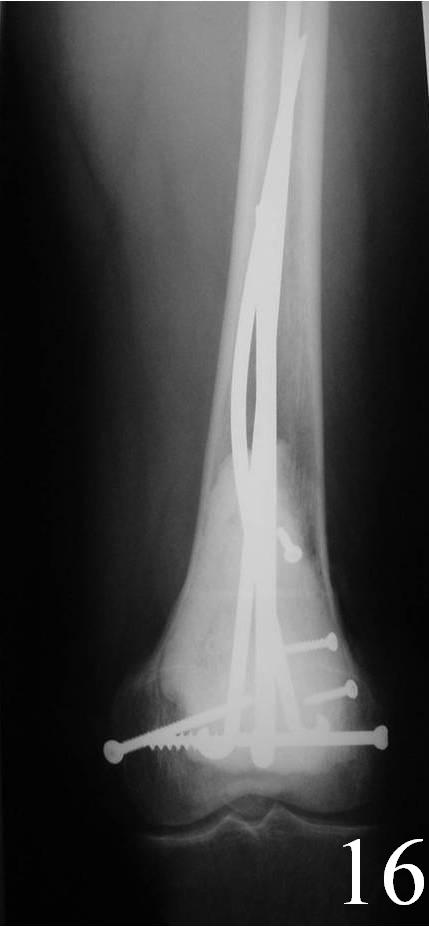

o Curettage, cement and possible internal fixation with hardware (Fig. 13, 14, 16)

Fig. 15 Cryosurgery of the tumor cavity where liquid nitrogen is poured into the cavity to kill microscopic cells.

Fig. 16 AP Xray of distal femur demonstrates fixation with Rush rods and cement.